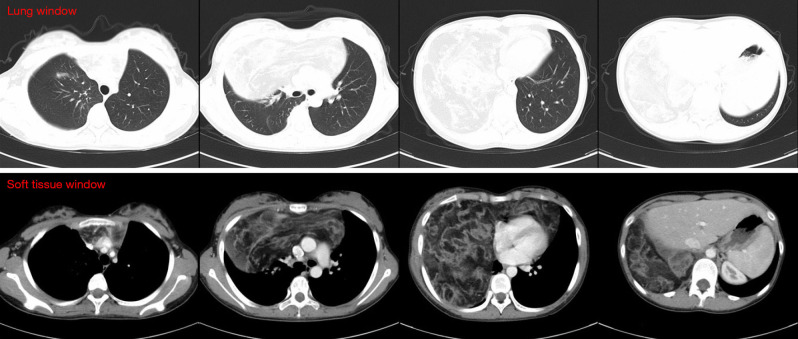

Case description: A teenage girl was diagnosed with a giant thymolipoma, which was discovered incidentally during a routine chest radiograph. Notably, the patient remained asymptomatic despite the tumor's considerable size and its apparent impact on surrounding thoracic structures. To facilitate a thorough preoperative assessment, a multimodal imaging approach was employed, including contrast-enhanced ultrasound (CEUS), computed tomography (CT), and magnetic resonance imaging (MRI). These advanced imaging techniques played a crucial role in delineating the tumor's extent, characteristics, and relationship to adjacent anatomical structures, thereby informing surgical planning. Ultimately, the tumor was successfully excised through a median sternotomy. Postoperative pathological examination confirmed the diagnosis of thymolipoma. Remarkably, after a follow-up period of five years, the patient showed no signs of recurrence and maintained a healthy status.